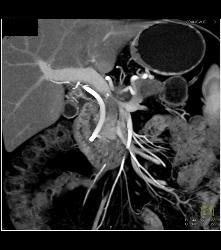

Pancreatic Cancer With Liver Metastases. Tumor Encases PV/SMV